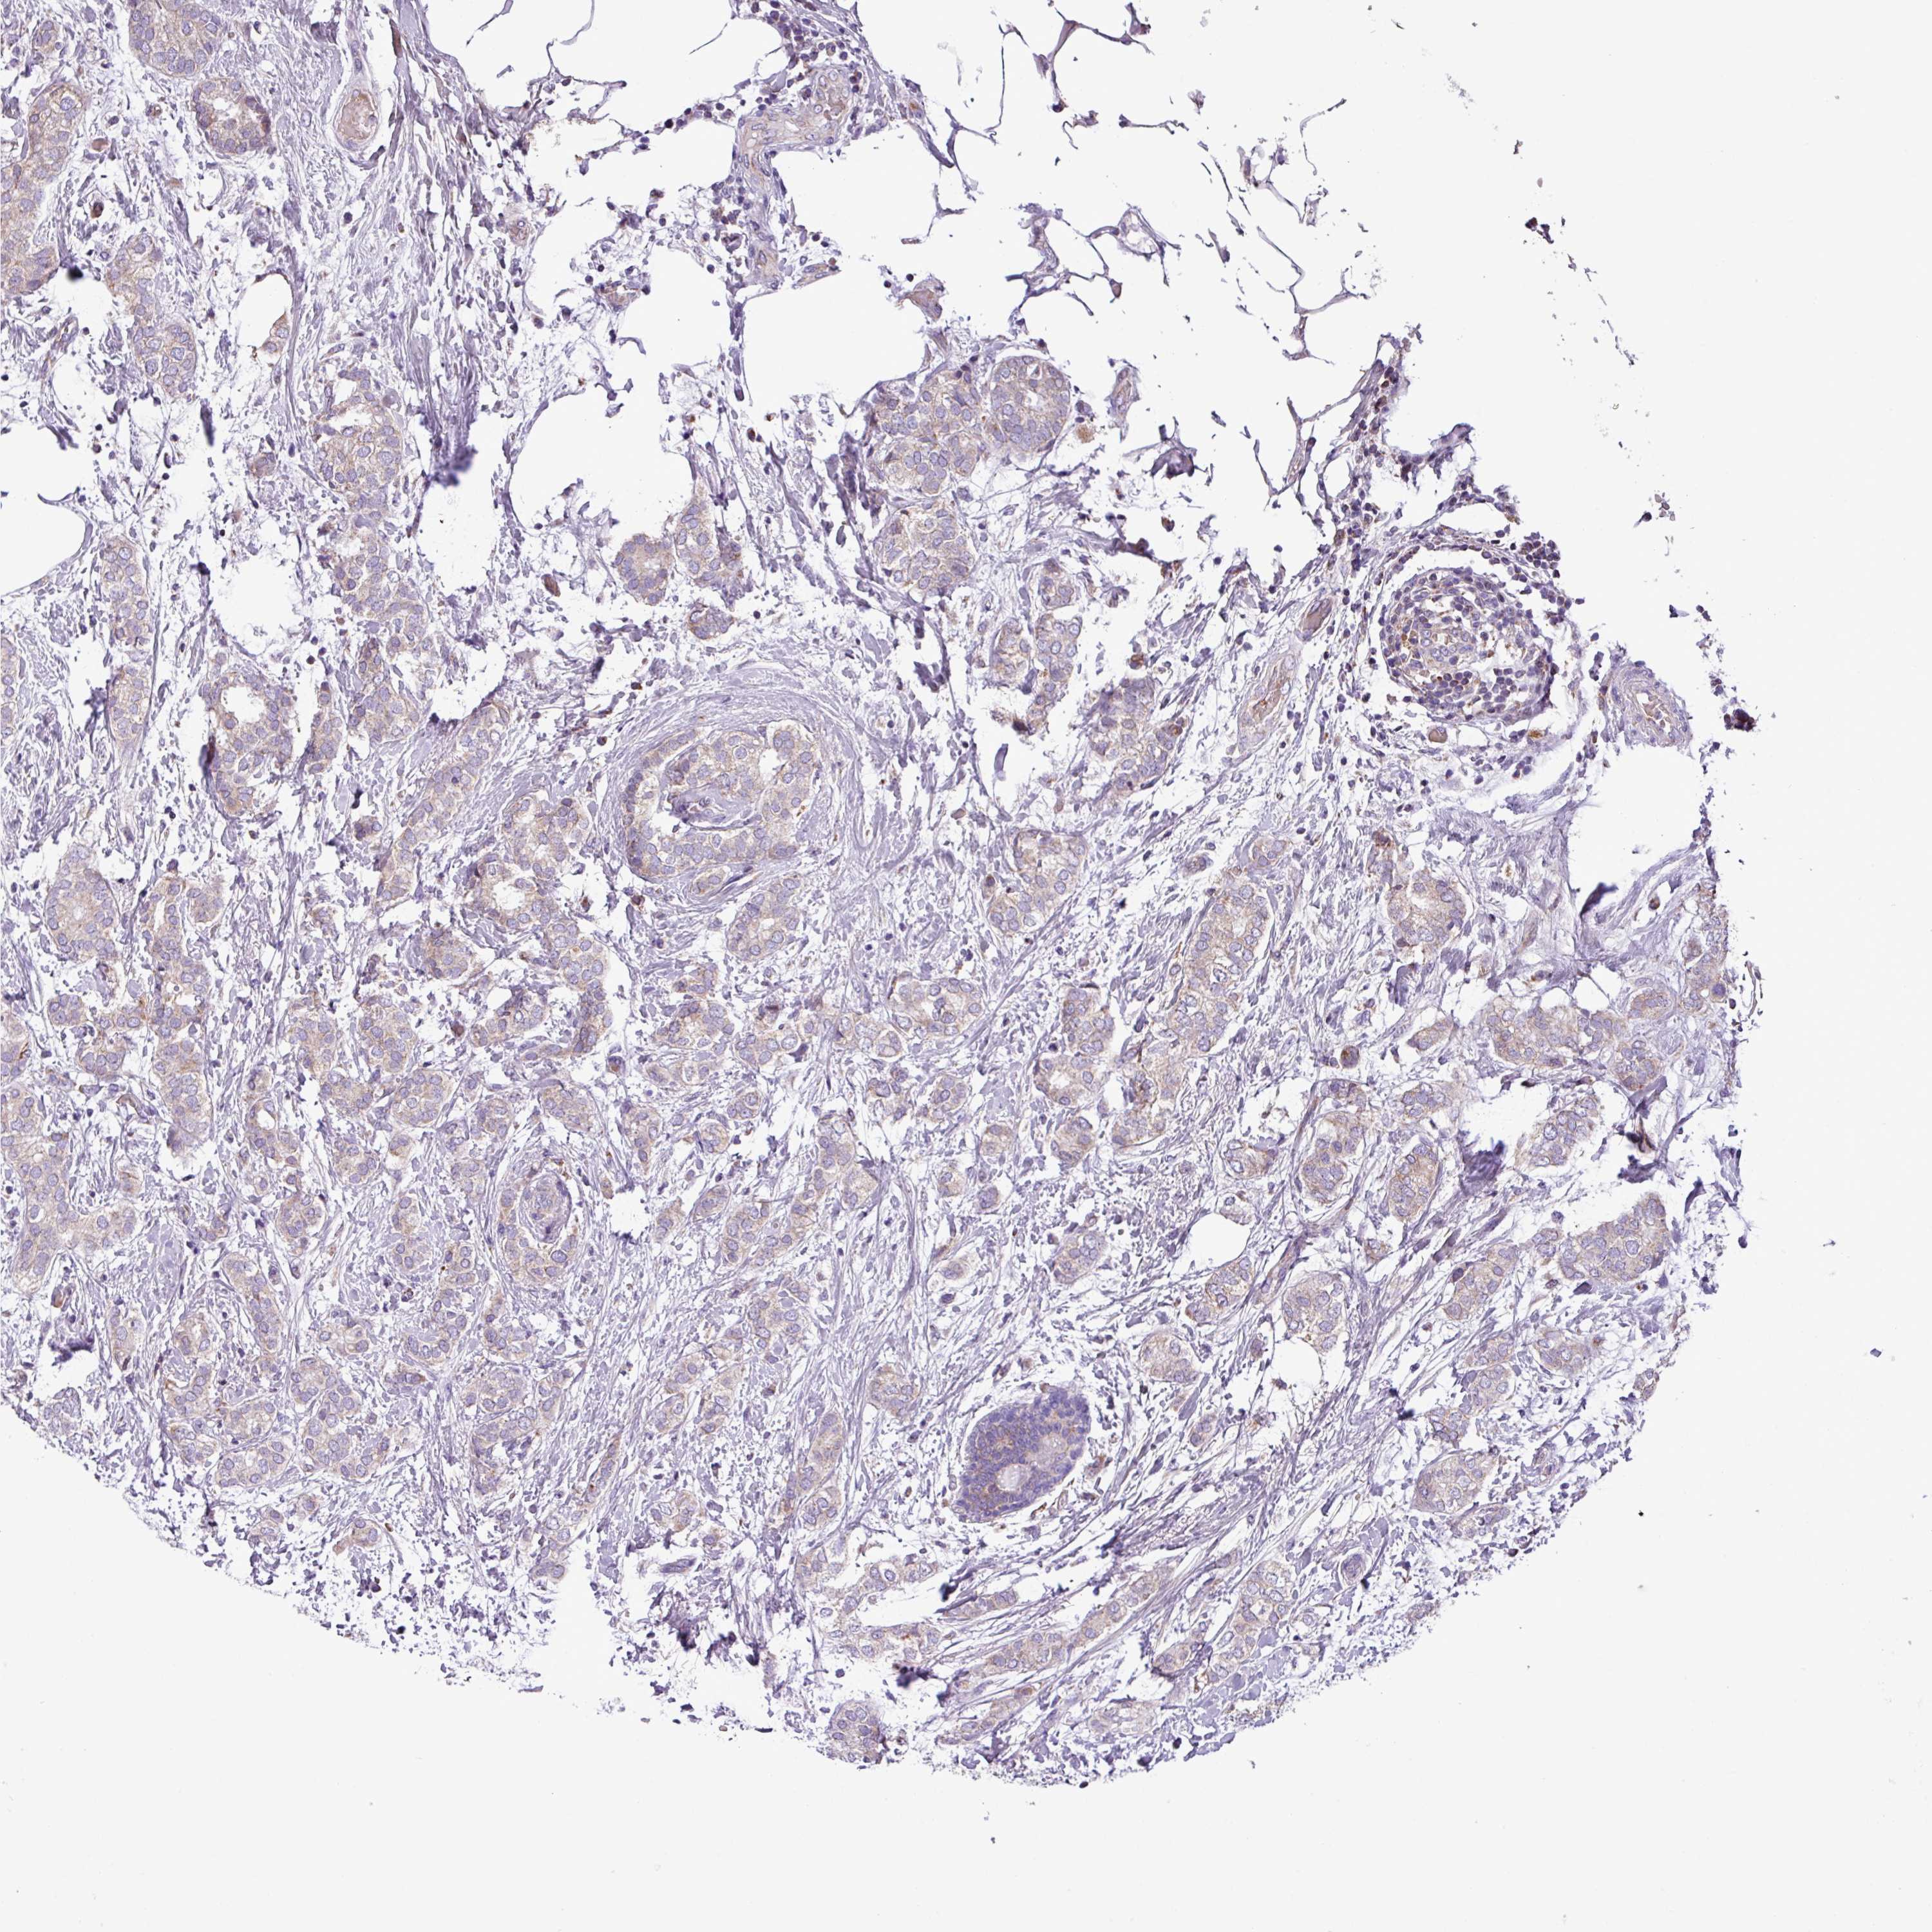

CANCER BREAST CANCER Show tissue menu

BRCA TCGA BRCA VALIDATION PROTEIN EXPRESSION